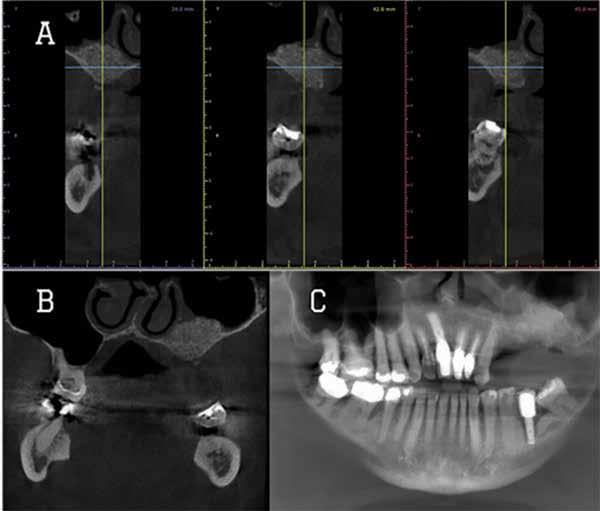

Magnetic resonance imaging (MRI) has been a staple in medicine and dentistry for many years. In dentistry, it serves a somewhat confined role in imaging the temporomandibular joints (TMJ) and occasionally the head and neck, including cysts or tumors. Dental MRI research and publications on these indications, as well as more “traditional” dental imaging tasks such as caries or periapical lesion detection, have progressed steadily since the mid-1980s, followed by a rapid increase in published papers in the early 2020s. These studies have long demonstrated the utility of MRI TMJ and cyst/tumor imaging, as well as the promise of MRI for essentially the entire range of dental imaging indications. Indications include caries, periapical disease, periodontal disease, growth and development/

The newly formed Orofacial MRI Center (OMRIC, dentistry.umn.edu/omric) at the University of Minnesota School of Dentistry is home to the first dental-dedicated MRI (ddMRI) unit in North America and the second installation of its kind in the world. Researchers Drs. Don Nixdorf and Laurence Gaalaas have an extensive track record in dental MRI research and development. Still, they are thrilled to have as an imaging tool one of the very first dental-dedicated MRI units, a Siemens MAGNETOM Free.

Max Dental Edition* MRI scanner. In collaboration with Dentsply Sirona and Siemens Healthineers, Nixdorf and Gaalaas secured a multi-year research agreement and constructed a physical imaging center around a Free.Max MRI unit. Beginning in early 2025, they initiated research studies to investigate the utility of ddMRI diagnosis in patients with endodontic, orthodontic and TMJ conditions. Such work will establish the utility of an experimental dedicated extraoral dental MRI coil and support proven indications for ddMRI imaging in endodontic, orthodontic, TMJ and other dental patient populations.

Proton density (left) and CBCT (right) images of apical lesion and furcation involvement at tooth #2. This tooth was clinically diagnosed with pulpal necrosis and a crack involving the furcation.

Proton density image showing improved image detail provided by dental dedicated MRI coil.

For those who need a refresher or those who have never truly understood how MRI works, the physics and engineering involved are remarkable. The four basic steps to performing MRI are 1) Put a patient or patient’s body part in a strong magnet field, causing protons (hydrogen nuclei) in the patient to align with the magnetic field. 2) Apply a radiofrequency (RF) pulse at a specific frequency, then, in a phenomenon of physics, all of the protons in the patient previously aligned with the magnetic field realign with the RF pulse and absorb some of the transmitted RF energy. 3) Stop the RF pulse and record any RF energy released back by the patient. It turns out that when tissue protons absorb RF energy, they release it back into their surrounding environment in two distinct ways (T1 and T2) and at variable rates based on surrounding tissue characteristics. Repeating this process multiple times while intentionally altering the initial strong magnetic field with secondary magnets (called gradient coils), all while recording this released signal with an MRI coil (think antenna) allows the system to back-calculate 1) a signal representing relative density of protons or other tissue characteristics and 2) the spatial location of that signal, all together letting us create diagnostic images representing anatomy, disease and at times, tissue function.

which perform notably better at imaging hard tissues such as bone and teeth, compared to more traditional MRI sequences.

While most dentists are likely familiar with the basics of how information is displayed on an MRI image, the adoption of ddMRI will require a mindset shift for virtually all dental team members who may utilize this new technology in their respective clinics. First, the grayscale is fundamentally different from that used for all X-raybased imaging. In MRI, soft tissues are commonly displayed as gray or bright white signals, while hard tissues, such as teeth and bone, are shown as very dark gray or black signals; air remains black. Furthermore, MRI offers the option to select from a variety of different sequences, each of which can produce a slightly different tissue grayscale and corresponding image. Some sequences, such as T1 or PD, do an excellent job of demonstrating detailed anatomical relationships. Other sequences, such as T2, do an excellent job of demonstrating the presence of fluid accumulation within tissues. Many available “Fat sat” or “STIR” sequences may selectively “zero out”, “suppress”, or “saturate” the signal of fat, which is traditionally very bright white on MRI images, to reveal the otherwise hidden signal from subtle fluid accumulation or inflammatory changes. Some of these specialized sequences may not accurately depict anatomic relationships, but are designed to be exceptionally sensitive to detecting inflammatory changes with a bright signal. The short T2 sequences mentioned above are beginning to depict the hard tissue differences between cortical bone and medullary bone, as well as the differences between tooth dentin and enamel. Developing, learning and using all these different sequence choices in concert is where the real research and diagnostic potential of ddMRI lies. t